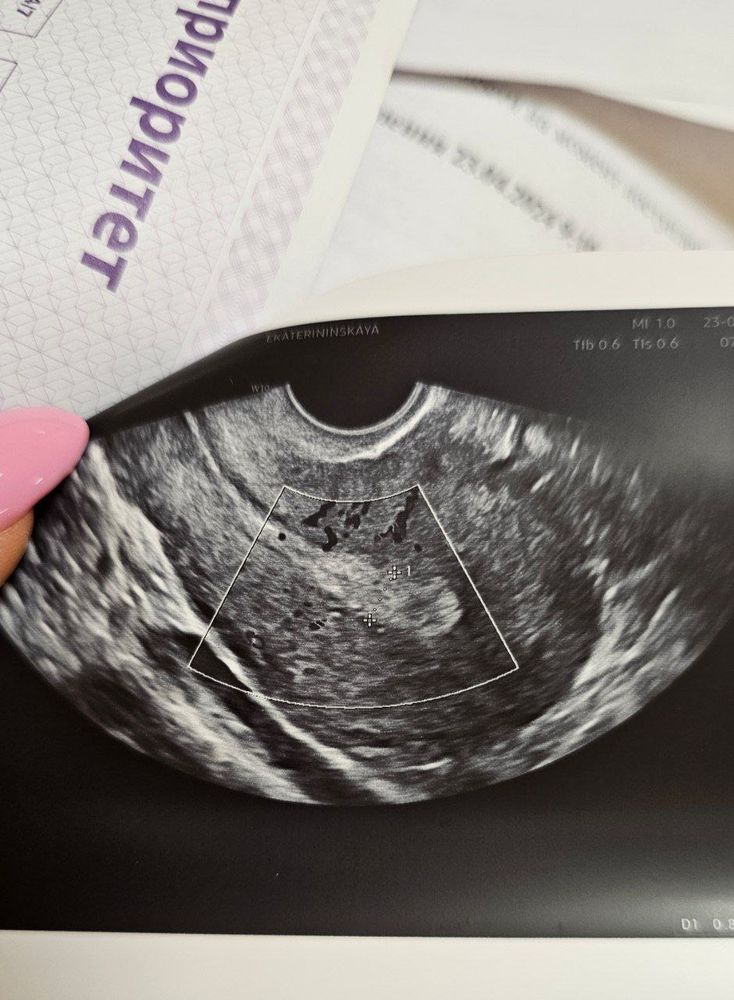

🔎На 37 дц не выдерживаю, иду на узи, чтобы понять - что вообще внутри происходит.

Она долго пытается найти левый яичник, очень больно, у меня слезы из глаз 🙈 В правом находит черную дыру, тоже долго смотрит. Говорит: овуляции не было, это фолликулярная киста.

Я говорю - я видела кровоток (экран перед моими глазами висел).

Она: это не то, остаточный.

Эндометрий однородный, а не трёхслойный, на вторую фазу, не похож на предменструальный.

В итоге все же это было желтое тело!!!! Просто очень большое, у меня обычно 23-25 мм в беременность (фото 5)